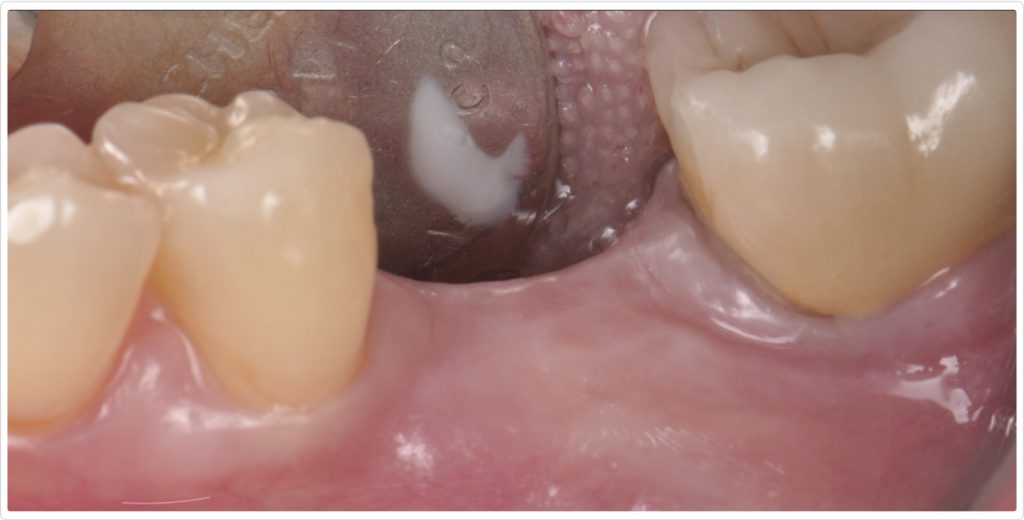

The patient, a 55-year-old woman with no significant medical history, presented with an edentulous site in the mandibular first molar region (area #19). The tooth had been extracted more than three years ago because of caries. Initial clinical examination (Figs. 1a and 1b) revealed a horizontal ridge defect and minimal keratinized mucosa at the site, posing challenges for implant placement and long-term stability.

A radiograph taken six months after the procedure (Fig. 7) showed satisfactory healing and bone integration around the implant, indicating successful osseointegration and stability of the grafted site. Clinically, a lateral view of the ridge (Fig. 8) revealed minimal keratinized tissue at the site, highlighting the need for further soft tissue management.

To address the deficiency in keratinized mucosa, a second-stage surgery was planned. A crestal incision was made at the edentulous site, not touching the adjacent teeth. A partial-thickness flap dissection was performed at the implant site, displacing the minimal keratinized tissue present at the lingual site (Fig. 9). Two divergent vertical incisions were made at the buccal area, leaving the connective tissue and periosteum attached to create a vascular surface for a free epithelialized graft. The cover screw was then removed, and a 5 mm healing abutment was placed.